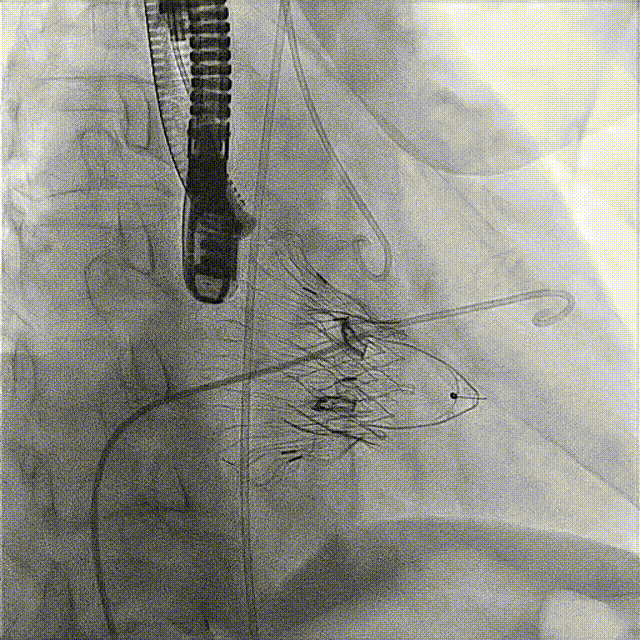

術后DSA

術前經(jīng)過全面系統(tǒng)的評估后,考慮患者存在高齡、心功能減低、三尖瓣瓣環(huán)重度擴張(三尖瓣極重度反流)等高危因素,因此廈心結構心團隊聯(lián)合超聲心動、麻醉及護理團隊,制定了詳盡的圍術期治療方案及術中治療難點預案。術中,由王焱院長主刀,在蘇茂龍主任超聲心動團隊的輔助,上海市第一人民醫(yī)院陸方林主任的協(xié)助下,僅用時30分鐘,即順利完成了三尖瓣原位置換的手術。術中患者血流動力學穩(wěn)定,術后即刻顯示LuX-Valve Plus瓣膜位置良好,固定穩(wěn)定,瓣膜功能正常,無瓣周漏。